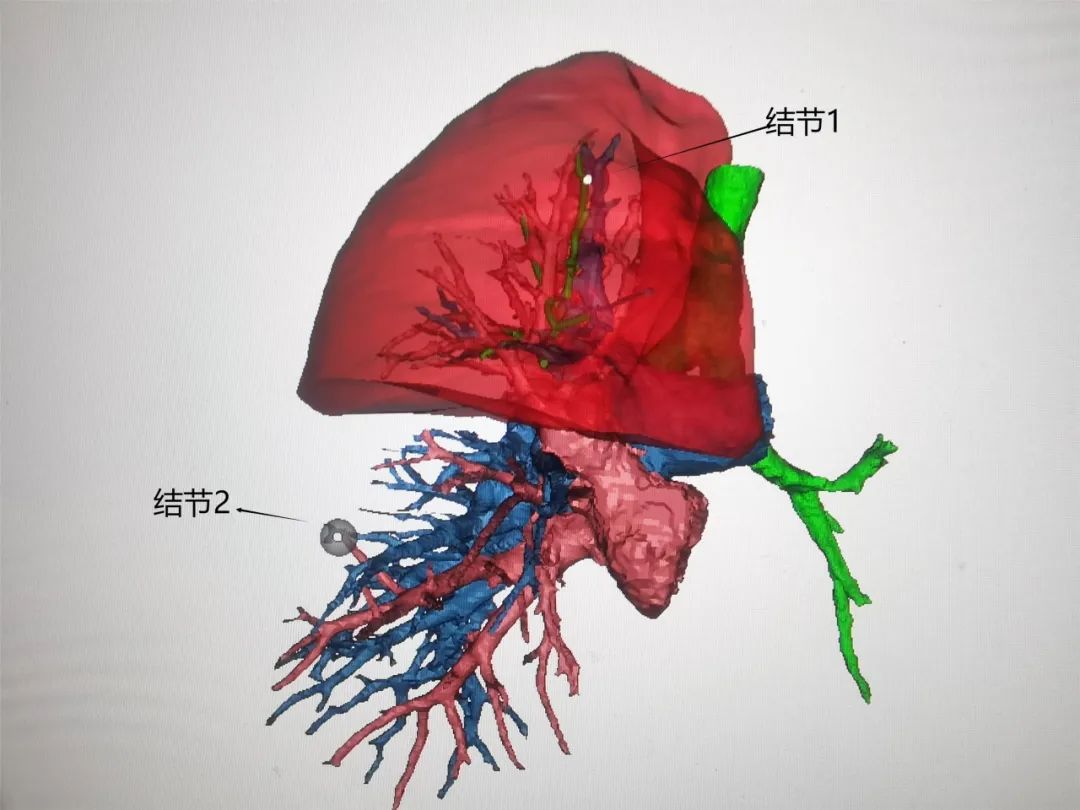

征得患者及家屬同意后,?我院胸外科團(tuán)隊(duì)通過術(shù)前CT影像繪制出該患者肺三維重建,施行了單孔胸腔鏡下右上肺尖段固有亞段切除(RS1a)+右下肺楔形切除,手術(shù)順利,切除標(biāo)本送病理均提示浸潤性腺癌,術(shù)后患者恢復(fù)良好。

關(guān)于肺小結(jié)節(jié)的精準(zhǔn)定位,精準(zhǔn)切除,有很多方法,像黃大爺右下肺結(jié)節(jié)用的就是手指觸摸定位法,右上肺結(jié)節(jié)用的就是三維重建定位法,今后我們還會(huì)闡述其他定位方法。